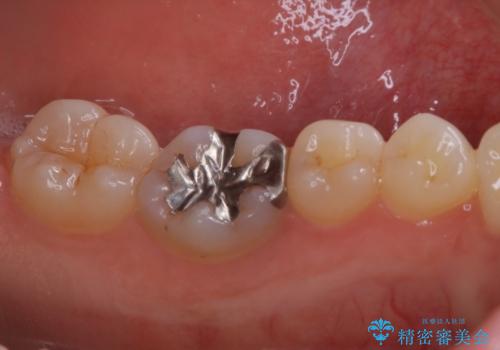

- 大きく口を開けると目立つ銀歯のやり替えをご希望された患者様です。適合のよいセラミックインレーで補綴することで、将来的な虫歯発生のリスクを最小限に抑え、機能面でも安心して使っていただけるようにしました

適合不良の補綴物は二次的な虫歯発生のリスクが高まります。

自費診療で用いられる材料は保険適応の材料に比べて、より精密で適合の良い被せ物作ることができるため、長期的な虫歯のリスクを大幅に減らすことが可能です。